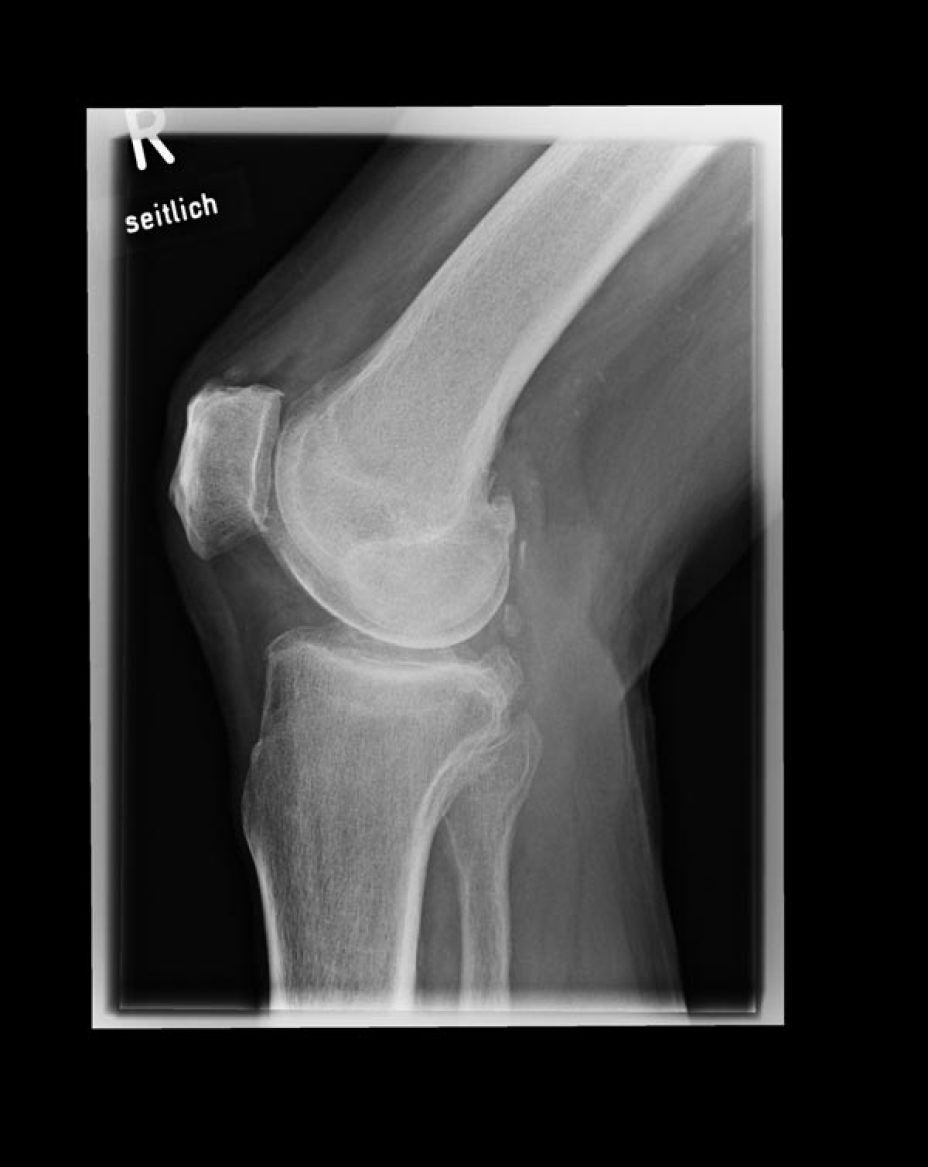

- Coxarthrose, Gonarthrose, Omartrhose sowei Polyarthrose (Gelenkverschleiß)

- 64% der Patienten mit Kniearthrose